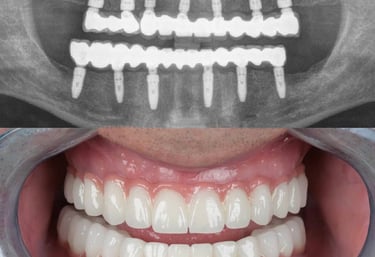

Implants

If you are missing one or more teeth, dental implants are the most reliable and natural-looking solution.

Implants act as artificial tooth roots, providing a stable foundation for crowns, bridges, or dentures. Benefits include:

• Permanent and durable replacement

• Natural function and aesthetics

• Preservation of jawbone and facial structure

At Dr. Teeth, we use advanced implantology techniques for safe, effective, and long-lasting results.